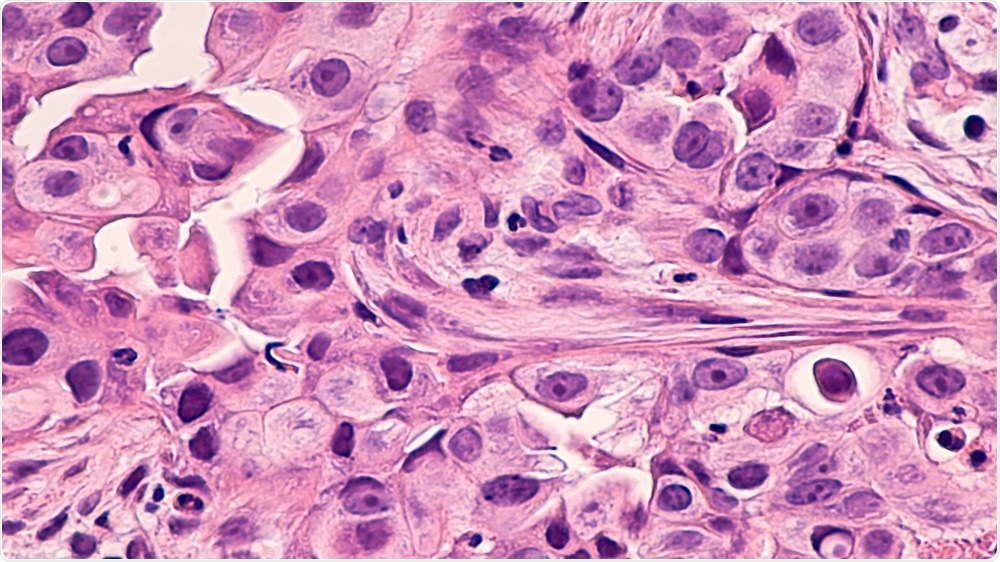

Credit: David Litman/Shutterstock.com

Currently, cancers are generally diagnosed using a tumor biopsy that is thinly sliced and stained with two vegetable dyes called haematoxylin and eosin. This “H+E stained” sample is analysed under a microscope and the severity of the cancer is graded by eye. .